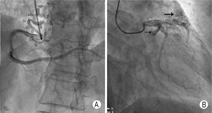

患者女,64岁。无任何治疗史,主因间断胸痛、心悸9个月入院。心电图示:窦性心律,Ⅱ、Ⅲ、avF导联ST段压低。实验室检查结果正常。超声心动图示:左室射血分数60%,室壁运动未见异常,二维超声显示左房、左室内径增大(左房39.9 mm,左室53.9 mm);彩色多普勒提示二尖瓣、三尖瓣中等反流;估测肺动脉平均压约为39 mmHg(1 mmHg=0.133 kPa),提示肺高压。选择性冠状动脉造影术未发现有意义的狭窄性病变,显示两处起源于右冠状动脉近段的冠状动脉瘘,以及另外两处分别起源于左前降支近端及左回旋支近端的冠状动脉瘘,肺动脉位置可见造影剂显影,考虑多支冠状动脉-主肺动脉瘘(图1)。外科手术证实该诊断,后经外科手术治疗成功封闭异常瘘口,院外随访3个月,患者胸痛、心悸症状消失。

对于本例患者,术前超声未发现瘘口,仅表现为左心增大。造影发现冠状动脉瘘后,回放患者超声图像,大动脉根部短轴观可见自左冠状动脉至肺动脉的异常分流及自右冠状动脉至肺动脉的异常分流(图2)。